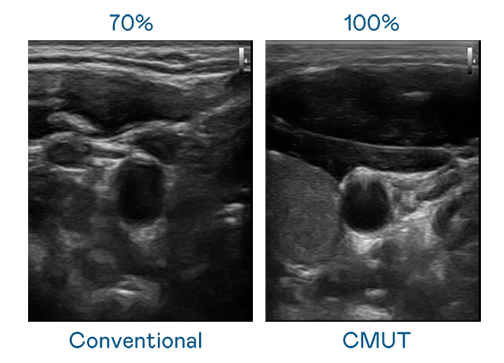

CMUT 技术是一种用电容式微机电元件来产生超音波讯号的技术。与传统 PZT 压电式技术相比,CMUT 频宽增加 30%,更宽频的超音波讯号让影像解析度大幅提升,是实现高影像品质医疗超音波扫描、促进精准医疗发展的关键技术。

超音波影像的解析度高低,首先取决于探头能发出的讯号频宽。星空无限mv在线看免费版中文版在线看 CMUT 可提供高清晰的超音波讯号,提供高频宽、高灵敏度、影像纹理细节更高的超音波影像,协助医护人员缩短影像判读时间及利用精准的医疗影像进行诊断。